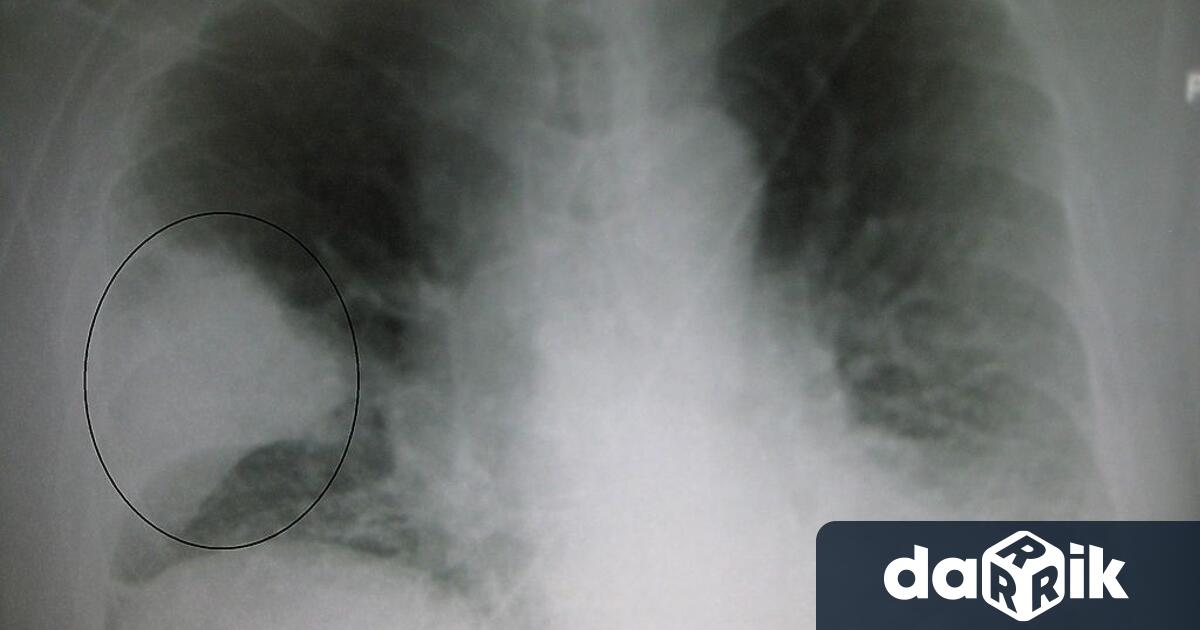

Пневмонията е възпалително заболяване на белите дробове, при което се нарушава естествения развой на дишане. Тя постоянно би трябвало да се смята за съществено заболяване, без значение че при съществуване на мощни антибактериални средства, най-често се изкарва " на крайник ". В взаимозависимост от защитните сили на организма, съпътстващите болести и възрастта тежестта на протичане варира от съвсем безсимптомни форми, до тежка дихателна непълнота с заплаха за живота на болния.

Целта на днешния ден е информиране и финансиране в световен проект по отношение на заболяването, от която умират най-вече деца под 5-годишна възраст в света. Според статистиката, единствено през 2015 година повече от 900 000 деца са умряли от това предотвратимо и лечимо заболяване, като 3 % от тях са новородени. Иновациите в диагностиката и лекуването на пневмонията са основни за попречване на детската смъртност и най-много за тези деца, които е най-трудно да бъдат достигнати. Например, извънредно значимо е да се откри нов способ за ранна диагностика на пневмонията в здравните заведения, където рентгените и лабораторните проби не са налични или са незадоволителни.